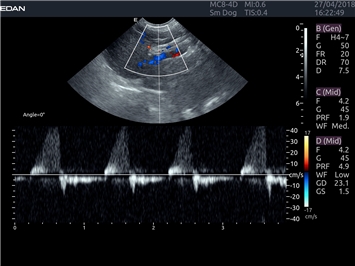

EDAN Acclarix LX4 VET представляет собой профессиональную ультразвуковую систему, специально разработанную для ветеринарных исследований. Сочетание стабильности, высокой производительности и эффективности делает эту систему идеальным выбором для современной ветеринарной практики.

Постоянно-волновой допплер:

Да

Импульсно-волновой допплер: